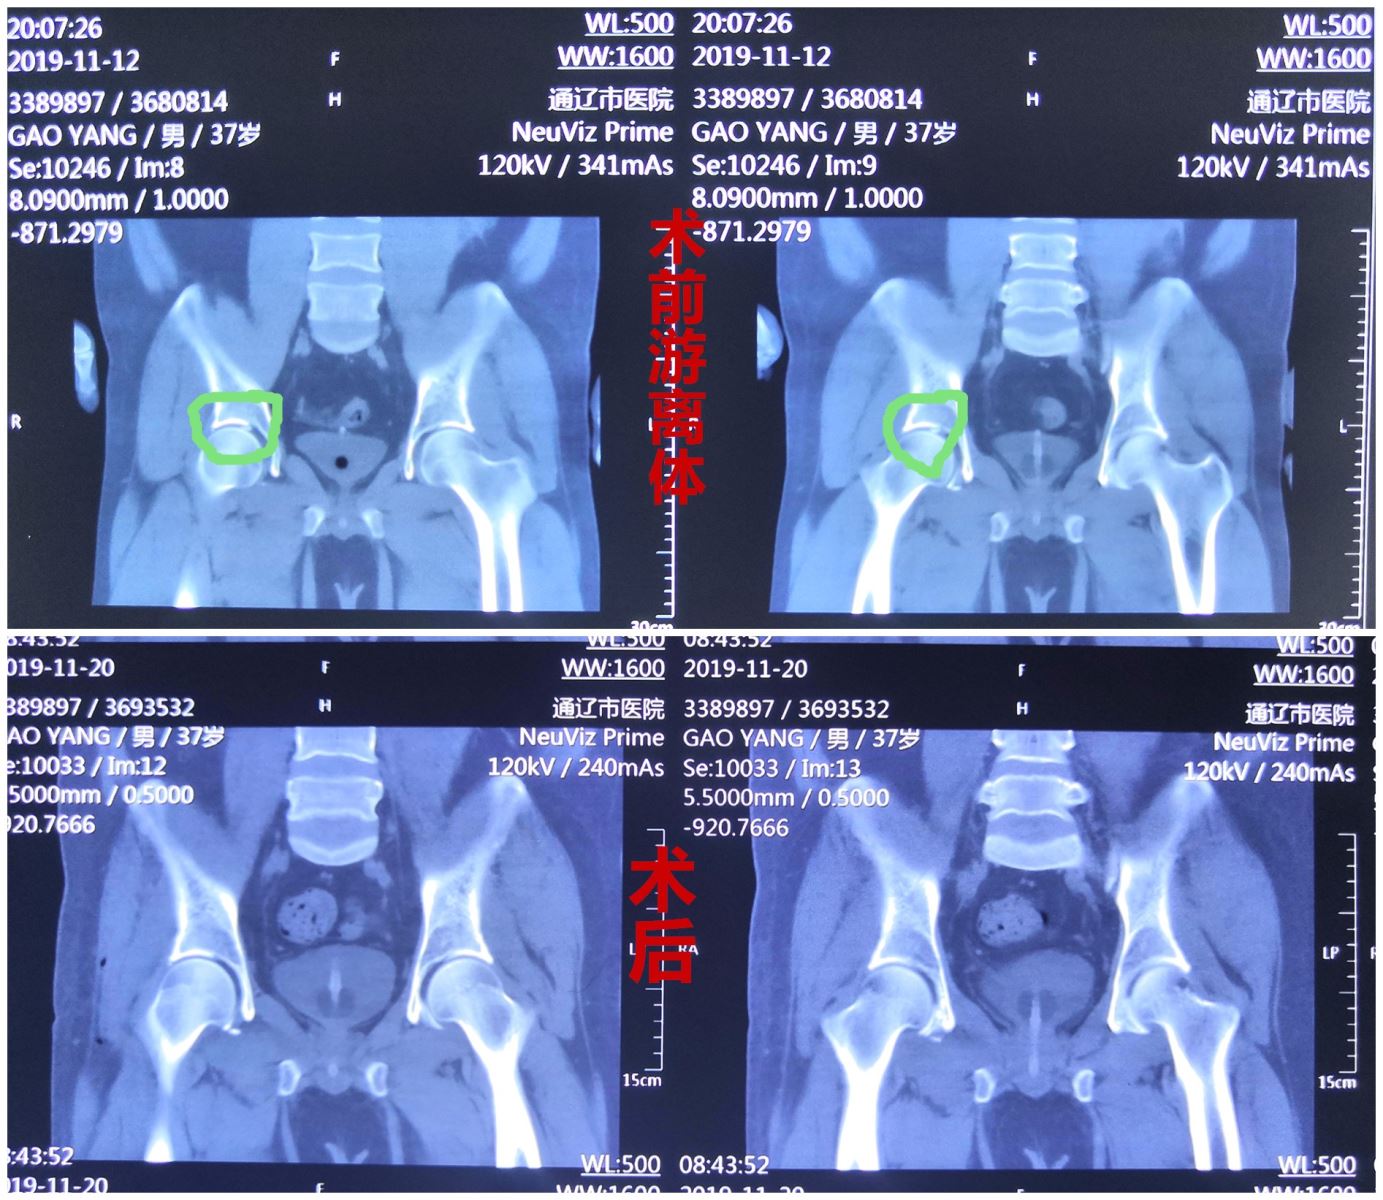

患者男性,37岁,因全身多发骨折于11月12日晚于我院骨四科行骨折内固定等治疗。其中髋臼骨折由于移位不大可行保守治疗,但股骨头撕脱的骨折块脱落到了髋关节腔,形成了髋关节游离体,若切开取出游离体创伤太大。为保障患者活动自如,骨四科医疗团队针对该患者病情,经反复讨论,确定了最佳的手术方案,决定运用髋关节镜技术,预采用侧卧位前入路非牵引床下髋关节镜游离体取出术。待患者生命体征平稳,征得患者知情同意后,手术由燕飞主任亲自主刀,在全麻非牵引床下为患者行侧卧位前入路微创关节镜游离体取出术。术中仅用1小时零5分,术后,患者髋关节活动障碍感明显消失。